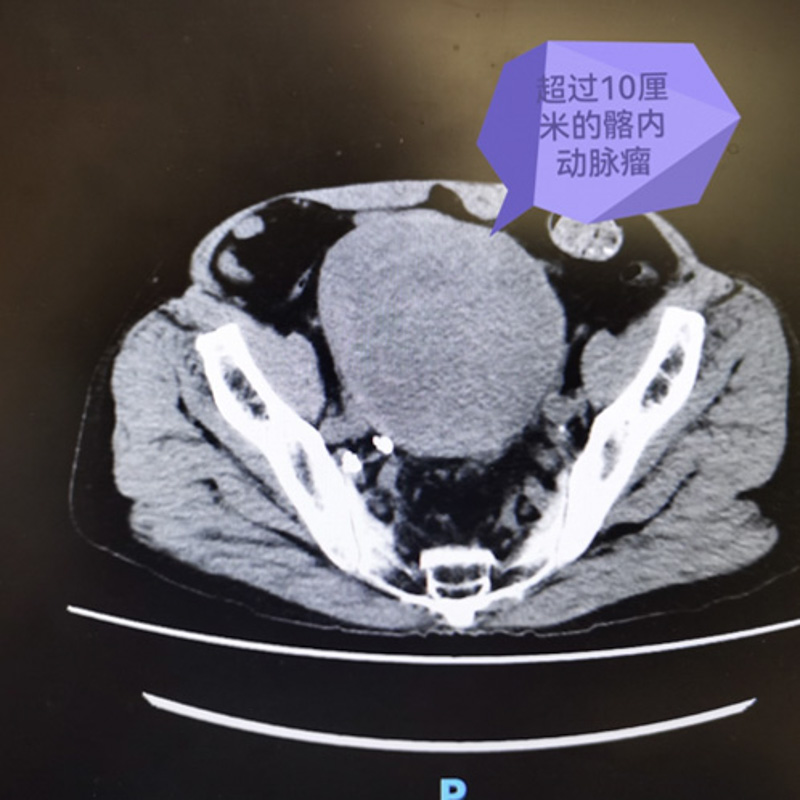

一年前,賈老伯逐漸感覺下腹部腫脹,伴有便秘及右側(cè)腰痛,平時(shí)在家務(wù)農(nóng)也沒太在意,隨著時(shí)間的推移,便秘情況越發(fā)嚴(yán)重,遂至當(dāng)?shù)蒯t(yī)院進(jìn)行檢查,發(fā)現(xiàn)盆腔內(nèi)有一巨大腫物,約15×12cm,情況不容樂(lè)觀。

為求進(jìn)一步治療,日前,賈老伯來(lái)到了柳州市人民醫(yī)院就診。了解到患者情況后,醫(yī)院立即組織各科專家開展MDT討論,患者被診斷為右髂內(nèi)動(dòng)脈瘤假性動(dòng)脈瘤壓迫結(jié)腸及右輸尿管引起的腸腔狹窄、右腎積水。巨大的髂內(nèi)動(dòng)脈瘤假性動(dòng)脈瘤猶如一枚定時(shí)炸彈,隨時(shí)有破裂大出血的可能。

據(jù)介紹,常見的動(dòng)脈瘤分三種:真性動(dòng)脈瘤、假性動(dòng)脈瘤及夾層動(dòng)脈瘤,假性動(dòng)脈瘤瘤體沒有完整血管壁結(jié)構(gòu),完全靠周圍組織包裹住破裂到血管外的血腫,非常容易破裂,危及生命。正常的髂動(dòng)脈直徑不過(guò)1厘米,而賈老伯的假性動(dòng)脈瘤直徑已經(jīng)達(dá)到15cm,任何一次咳嗽、便秘、撞擊或提重物都可能導(dǎo)致瘤體破裂。